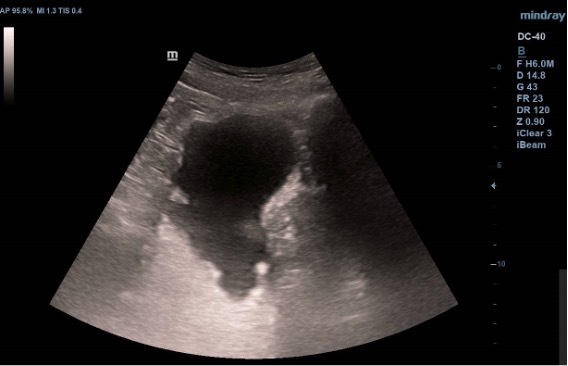

Ecografía vesical: Pared irregular, múltiples lesiones polipoides, la mayor (2.07 cm) en pared posteroinferior. Una lesión polipoiea dependiente de la próstata de 1,6 cm. Otra lesión más craneal en pared posterior de 1.26 cm, y cerca de uréter derecho una de 2 cm.  Además, varias lesiones polipoides más pequeñas en cara anterior y lateral derecha.

La citología confirma un Carcinoma urotelial de alto grado. En el UroTC se confirman múltiples lesiones polipoides endoluminales sugestivas de neoplasia. El paciente está pendiente aún de completar el estudio para iniciar el tratamiento.